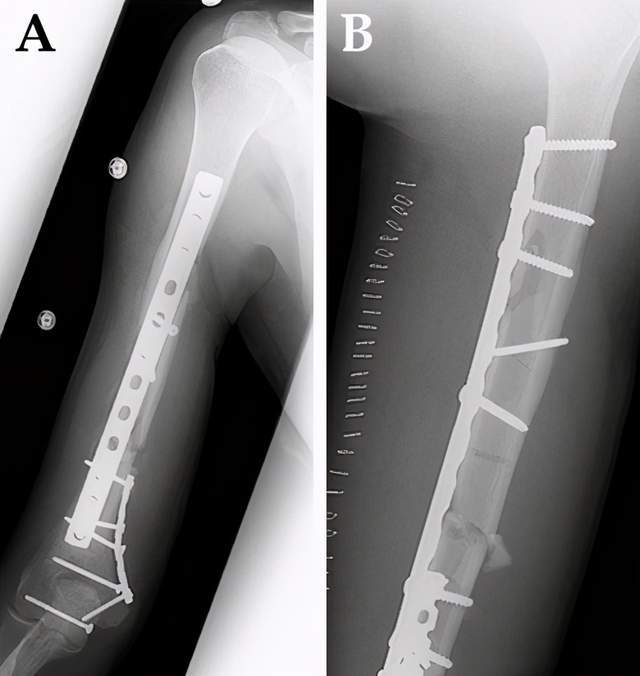

袁林林 肱骨中下段双钢板

单钢板和双钢板固定肱骨远端骨折效果相当